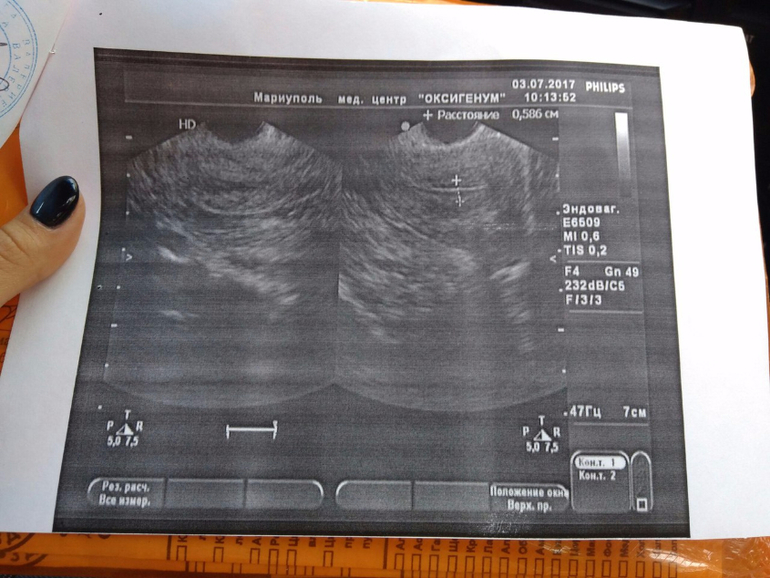

Моя первая фолликулометрия

ФолликулометрияШел 7ДЦ, а я шла на фолликулометрию...) Обнаружили у меня миом.узелок 16,5*15мм, что ни день - то новости...

В протоколе написала кучу страшных слов, девочки, помогите расшифровать, ПЛЗ!!!

Жидкостные включения в яичниках (4-10мм и 4-8мм) - это фоллики или кисты? Эндоцервикс неск. уплотнен в средн. трети - это как, это что?